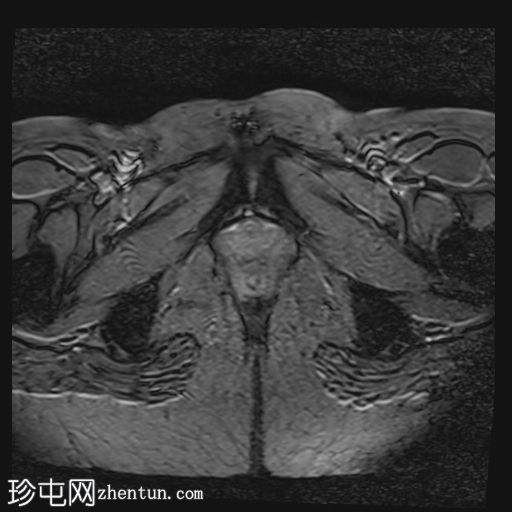

轴位

T2血流加权像

MRI特征符合剖宫产术后瘢痕子宫内膜异位症,表现为特征性T1高信号伴T1FS持续存在,T2低信号伴内部高信号灶,病灶边缘浸润于腹前壁肌肉内,以及对比增强。

在磁共振成像(MRI)上,瘢痕子宫内膜异位囊肿通常表现出与盆腔子宫内膜异位病灶相似的影像学特征。值得注意的是,它们在脂肪抑制T1加权像上表现为高信号强度区域,对应于异位子宫内膜腺体和出血。